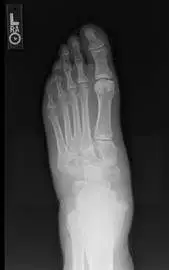

The following images are plain x-ray films of individuals who had Charcot deformities occur, which then causes significant problems with ambulation and pressure and abnormal aspects of the foot and ankle that lead to pressure ulcerations, further complicating the overall picture and the patient's health. Once Charcot arthropathy occurs it has phases beginning with the acute phase, which is the collapse of the foot or other involved joint, then the quiescent phase in which the process begins to slow down and the coalescent phase, which begins to stabilize the bones and joints in the position that they end up in. It is important to address this condition if possible before this phase occurs to allow correction of the deformity and the body's natural tendency to heal the process with the foot in the corrected position.

In the picture below one can see the bone in the middle of the foot pointed upward and displaced because of the breakdown of the middle of the foot. The bone (cuneiform) has to be put back into position and held in that position to allow healing.